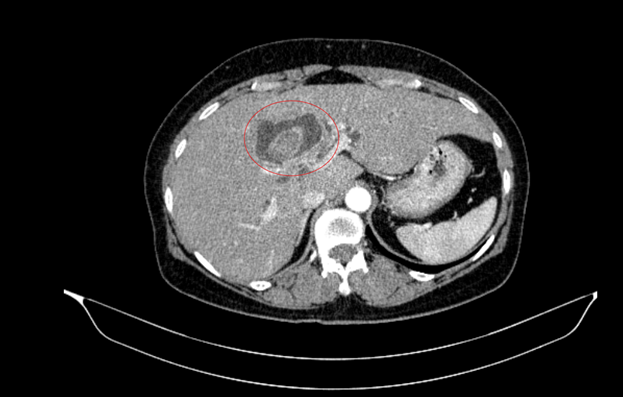

Bệnh nhân nữ, 59 tuổi, nhập viện trong tình trạng vàng da, ngứa và đau vùng hạ sườn phải kéo dài. Kết quả chẩn đoán hình ảnh cho thấy tổn thương đường mật trong gan kèm sỏi và giãn đường mật.

Trong quá trình thăm khám toàn diện, nội soi tiêu hóa phát hiện thêm một khối u tại đại tràng lên. Kết quả sinh thiết xác định đây là ung thư biểu mô tuyến.

Sau hội chẩn đa chuyên khoa, các bác sĩ xác định bệnh nhân mắc đồng thời hai ung thư nguyên phát, thay vì một khối u di căn. Cụ thể:

- Ung thư đại tràng phải: Giai đoạn sớm (IA), chưa di căn hạch

- Ung thư đường mật trong gan: Giai đoạn tiến triển (IIIB), có xâm lấn và di căn hạch